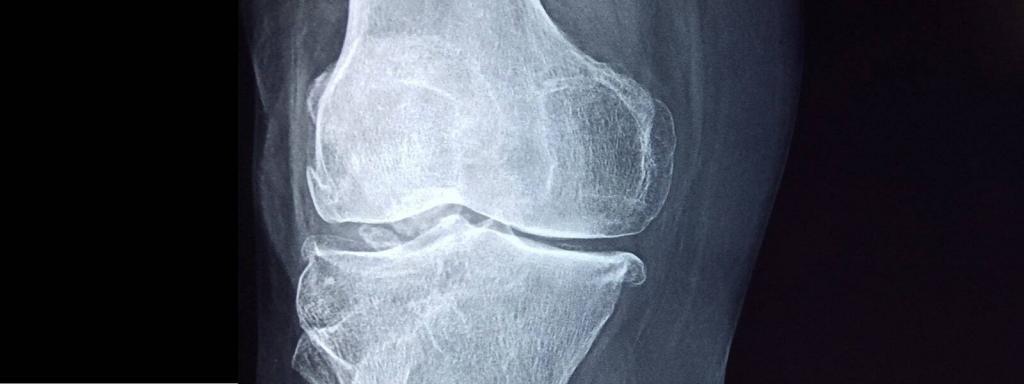

Адам ағзасынан бөлек сүйек тінін жасап шығаруға болама? Қазақстандық ғалымдар осыған жауап беретін бірегей жобаны бастады. Профессор Дана Ақылбекова жетекшілік еткен Назарбаев университетінің бір топ ғалымы адам сүйегін өсіріп оның 3D моделін басып шығаруға мүмкіндік беретін тың технология жасап шықты. Бар үрдіс швециялық принтердің көмегімен жүзеге асырылады.